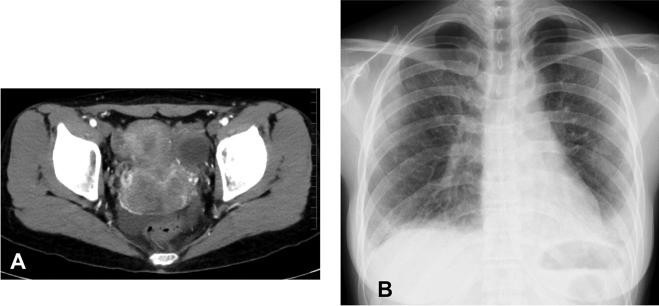

The anti-melanoma differentiation-associated gene 5 (MDA-5) antibody is a marker of clinically amyopathic dermatomyositis (CADM) and rapidly progressive interstitial lung disease (ILD) with acute respiratory failure. A 35-year-old woman with cervical cancer showed Gottron's papules, severe hypoxemia, and diffuse ground-glass opacities on chest computed tomography. She was diagnosed with rapidly progressive ILD associated with CADM. Her serum was positive for the anti-MDA-5 antibody. Combination therapy with corticosteroids, immunosuppressants, and direct hemoperfusion using polymyxin B-immobilized fiber column (PMX-DHP) improved her respiratory dysfunction. Eventually, surgery for the cancer was performed successfully. This is the first case to demonstrate the efficacy of PMX-DHP for rapidly progressive ILD with anti-MDA-5 antibody-positive CADM and a malignancy.

抗黑色素瘤分化相关基因5(MDA-5)抗体是临床无肌病性皮肌炎(CADM)和伴有急性呼吸衰竭的快速进展性间质性肺病(ILD)的标志物。一名35岁的宫颈癌女性出现Gottron丘疹、严重低氧血症,胸部计算机断层扫描显示弥漫性磨玻璃影。她被诊断为与CADM相关的快速进展性ILD。她的血清抗MDA-5抗体呈阳性。使用多粘菌素B固定纤维柱(PMX-DHP)进行直接血液灌流联合皮质类固醇和免疫抑制剂治疗改善了她的呼吸功能障碍。最终,成功进行了癌症手术。这是首例证明PMX-DHP对伴有抗MDA-5抗体阳性CADM和恶性肿瘤的快速进展性ILD有效的病例。